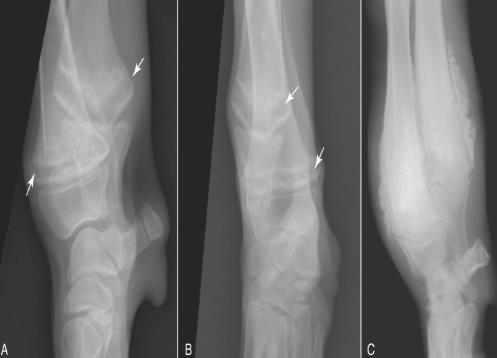

X光线通常显示病变骨头的变化,例如与生长板平行线的外观,骨密度的变化以及生长板周围的钙化。

肥大性骨营养不良也称为骨骼坏血病,Barlow氏病或Moller-Barlow氏病。最早是在1930年代中期的文献记载中出现。发病部位通常集中在桡骨、尺骨周围的生长板和胫骨等长骨的干骺端。尽管它主要只影响前两条腿,但也有可能发生在爪子,肋骨和下颌中。

前腿(靠近生长板的区域)疼痛和肿胀是最明显的迹象,但这取决于疾病的严重程度。 然而更严重的时候,小狗会表现出厌食症,体重减轻,发烧和抑郁,无法站立,脊柱弯曲,并拒绝在肢体上承受重量。